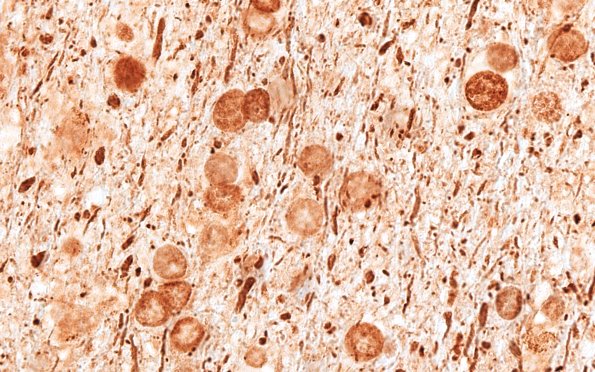

High magnification of axon fragments and spheroids. (NF IHC)